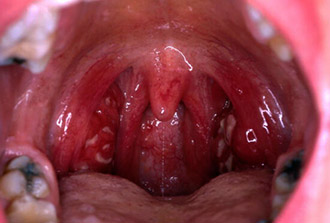

- Наличие беловато-жёлтых точек или налётов на миндалинах в виде «островков» или плёнок.

Плёнки характерны для лакунарной ангины — они не выходят за пределы миндалин, и при их удалении слизистая оболочка не кровоточит. Это важный дифференциальный признак, который помогает отличить обычную (классическую бактериальную) ангину от дифтерии, при которой требуется не только антибактериальная терапия, но и существует риск нарушения дыхания (дифтерийный круп).

Стрептококковая ангина является абсолютным показанием для назначения антибактериальных препаратов.